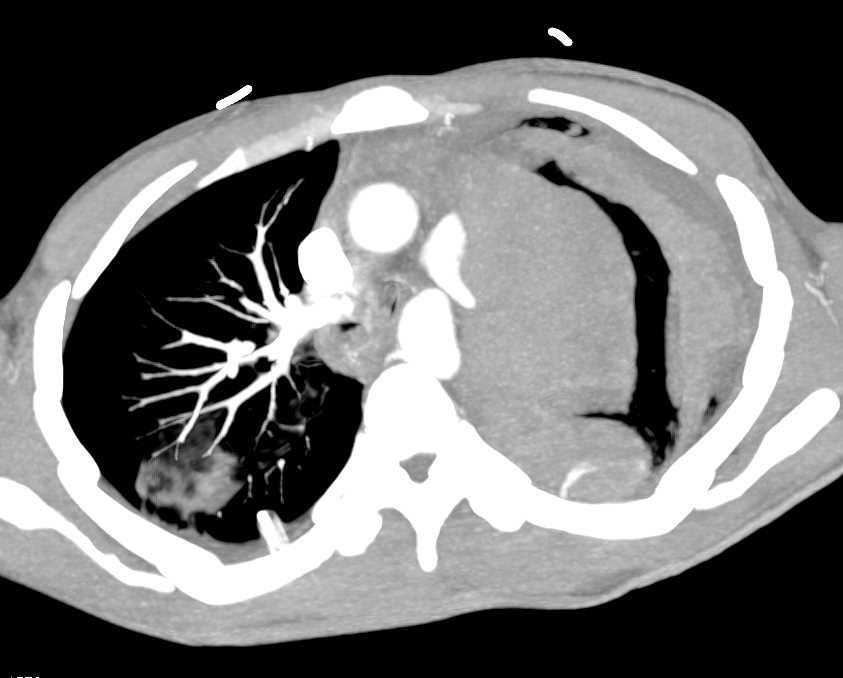

Pleural Based Hematoma